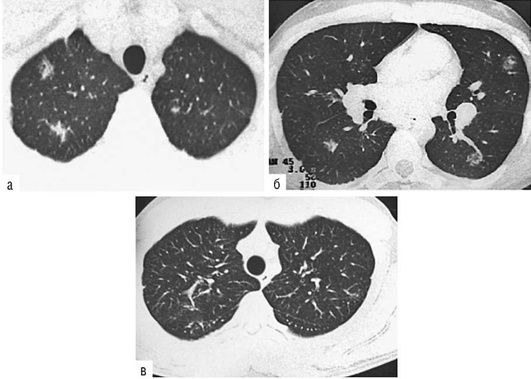

Лучевые методы исследования. Рентгенологическая картина при ЭТА зависит от стадии заболевания. В начальной фазе выявляются признаки отека интерстициальной ткани легких и распространенные мелкоочаговые затенения. При прогрессировании процесса формируются двусторонние изменения легочного рисунка по типу интерстициального фиброза, преимущественно в нижних отделах легких (рис. 2.28). В далеко зашедших случаях определяется мелко- и крупноячеистая деформация легочного рисунка. Описаны случаи, когда единственным рентгенологическим признаком болезни был односторонний плевральный выпот. Отсутствие каких-либо изменений на рентгенограммах отнюдь не исключает ЭТА. Так, при бериллиозе у 23-59% больных может выявляться умеренно выраженная двусторонняя лимфоаденопатия, а в ряде случаев - рентгенотрицательная форма бериллиоза (Dweik R.A., 2015). У 30% из 71 больных ЭТА, наблюдавшихся нами в клинике пульмонологии, в момент обследования изменений на рентгенограммах не было (Орлова Г.П., 2019). Группа больных ЭТА была обозначена условно как рентгенотрицательная группа. Уточнить диагноз помогает КТ легких, выявляющая интерстициальные изменения в легочной ткани по типу «матового стекла», усиление и деформацию легочного и сосудистого рисунка (рис. 2.29), фиброзные изменения тяжистого и звездчатого типов, на поздних стадиях - «сотовое легкое». ВРКТ выявляет «матовое стекло» и другие изменения в легочной паренхиме, которые не видны при обычном рентгенологическом исследовании. Но даже ВРКТ не всегда выявляет изменения в легочной ткани. Так, в 25% случаев гистологически подтвержденного хронического берил-лиоза легких ВРКТ была нормальной (Dweik R.A., 2013; Амосов В.И., Сперанская А.А., 2015; Amanullah S. et al., 2015).

Проведенное нами динамическое исследование КТ-паттернов у 42 больных ЭТА показало трансформацию отдельных типов интерстициальных пневмоний по мере прогрессирования патологического процесса в фиброзную НСИП или ОИП (рис. 2.30), что подтверждает объединительную концепцию интерстициальных пневмоний вне зависимости от этиологического фактора, которые являются не отдельными нозологическими формами, а стадиями течения фиброзирующего процесса в легких (Илькович М.М., Новикова Л.Н., 2018; Орлова Г.П. и др., 2019).